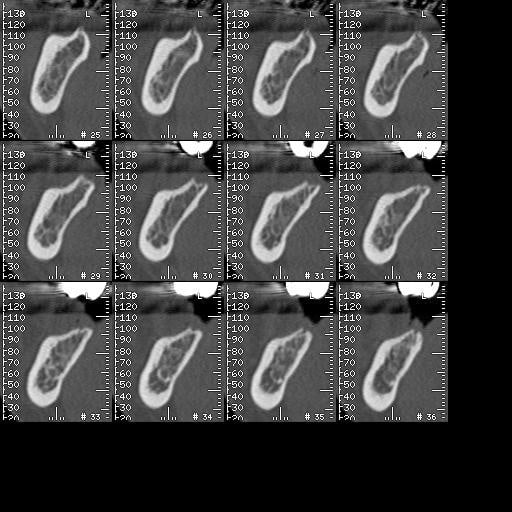

A défaut d'une chir en direct .. voilà une petite histoire en photos ou comment en 90 minutes passer d'un partiel résine à ...7 implants sur provisoires..stabilité primaire 60N grace à la technique MIMI ( oui.. post spécial ce Week end)..:)

Maintenant concernant la demande de scans : je poste ce cas, une patiente vient me voir avec son scan car elle a consulté d'autres "spécialistes" et on lui refuse la pose d'implant secteur 4 où alors avec greffe préalable..Ca se discute..pas de temps à perdre je sais faire autrement..

Avec la chir trans gingivale technique MIMI ( Oui..un post sur la technique bientôt ..) j'ai pu placer deux 3,5/8mm..aurai je eu le meme résultat avec un lambeau..j'en doute..Les couronnes sont en titane. Recul clinique 2 ans ras. Simple efficace rapide moins onéreux satisfaisant pour le praticien et la patiente..